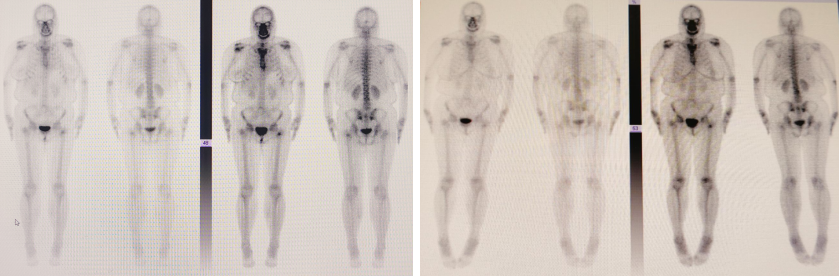

➤ 骨转移管理与疗效评估:

2024年4月23日,全身骨扫描提示出现右侧髂骨、L5椎体等新发骨转移。左侧股骨粗隆局部放射性骨肿瘤病灶,较前(2022年12月2日)大致相仿。随即开始使用双膦酸盐进行骨保护治疗,后转为地舒单抗治疗。

2025年1月9日复查骨扫描,显示此前(2024年4月23日)新发的右侧髂骨及L5椎体转移灶未再显影,骨转移情况显著好转。